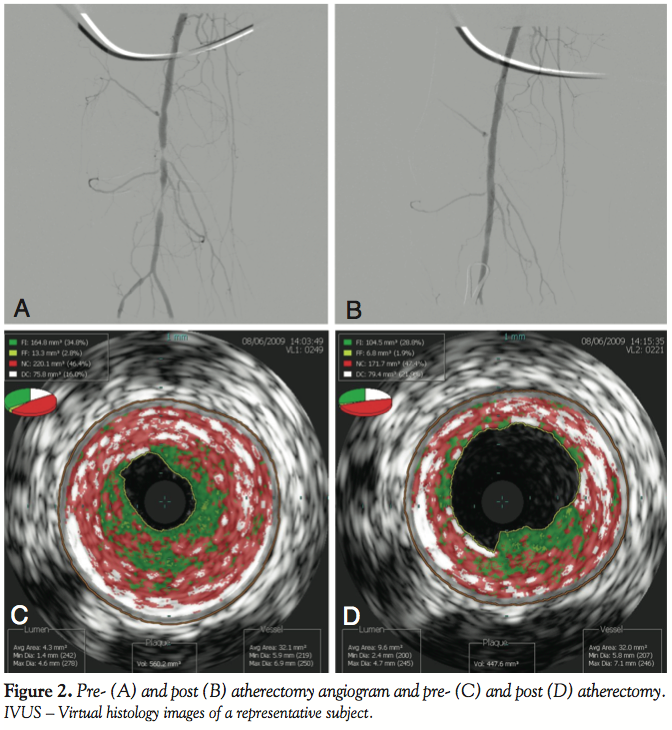

IVUS analysis of plaque volume, lumen volume, and vessel size. Figure 1 shows the percent composition of the plaque pre- and post-RA. Overall, the mean total plaque volume decreased by 56.6 mm3 (479.8 ± 172.5 mm3 to 423.2 ± 156.6 mm3; p < 0.0001), which resulted in a mean luminal volume increase of 64.3 mm3 (148.4 ± 84.1 mm3 to 212.7 ± 72.1 mm3; p < 0.0001) (Table 2). This was achieved without a significant Dottering effect with either technique, as evidenced by the

virtually unchanged vessel volume before and after treatment (628.3 ± 158.5 mm3 to 635.9 ± 169.0 mm3; p = 0.22). An angiogram and virtual histology pre- and post-atherectomy of a representative patient is shown in Figure 2. Overall, there was a 43% increase in the size of the lumen despite only reducing the total plaque burden by 11.8%.

Virtual histology analysis of plaque composition. The lesions were primarily fibrotic in nature, with an average total plaque volume of 64%. Fibro-fatty plaque formed 15% of the total plaque volume on average, whereas necrotic core and dense calcium formed 25% and 11%, respectively. Post-treatment, of the plaque remaining in the vessel, the percentage of fibrotic plaque burden remained at 47% and fibro-fatty plaque accounted for 12%. However, the proportion of necrotic core and dense calcium actually increased to 28% and 13%, respectively (Figure 1).